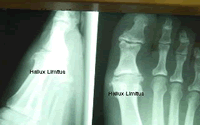

Hallux Limitus or Stiff Great Toe

This

problem stems from several factors including abnormal pattern of walking,

long first metatarsal bone, arthritis, injury, pronation or a combination.

The problem usually leads to pain and degenerative arthritis of the

joint. It can be addressed with a custom orthotic or shoe and / or surgery.

If this problem is not addressed it can create problems in other joints

such as ankles, knees, hips and back. A "rocker bottom" type shoe can

also help this problem. See your podiatrist for evaluation

of this problem.